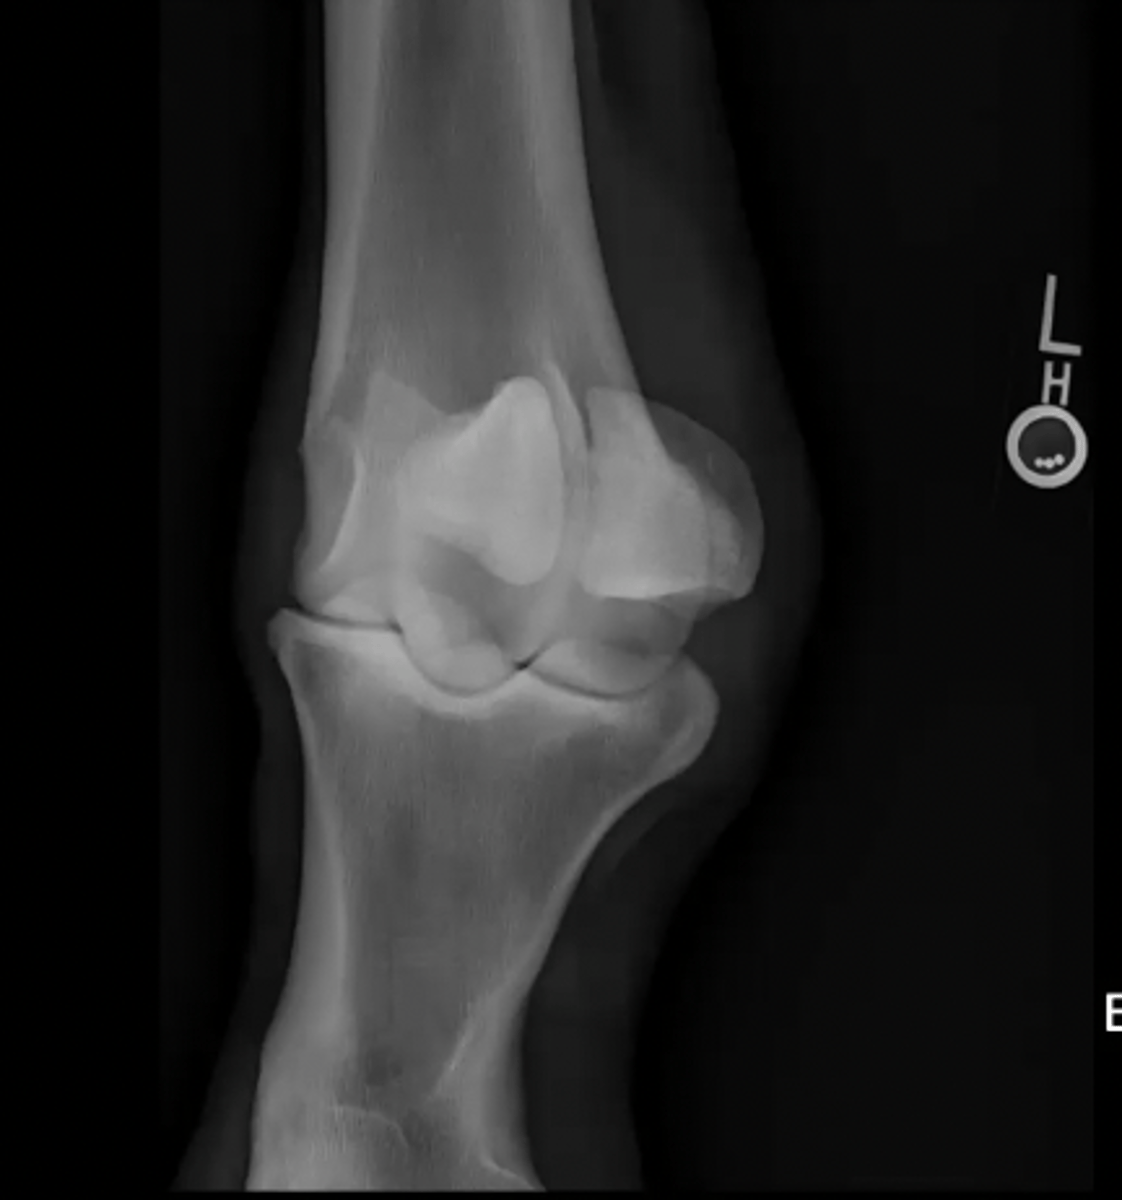

lateral canine elbow

What is the view of this image?